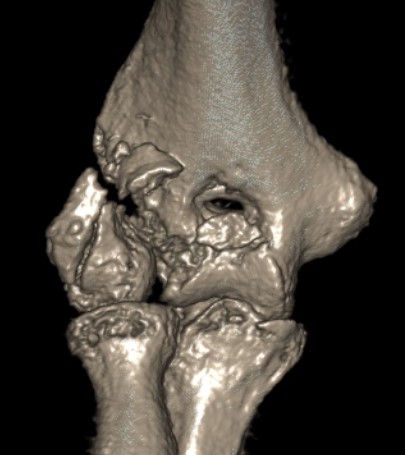

Dubberly Classification

Type I Type Ii Type III

Capitellar fracture

Capitellum + trochlea fracture

In one piece

Double arc sign seen on xray

Capitellum + trochlea fractures

In two separate pieces

Double arc sign on xray